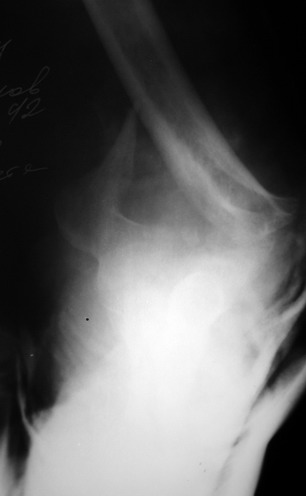

Солидарен с мнением обоих Александров (Челнокова и Рыкова): точную репозицию такого перелома вряд ли удастся выполнить закрыто. Даже во время открытого вмешательства это сделать непросто. Неслучайно предложен костно-пластический доступ с временным отсечением локтевого отростка. И по методу фиксации согласен с Александром Челноковым: 2 пластины. В качестве примера привожу рентгенограммы одного из наших пациентов с аналогичным повреждением.

С уважением, А. Золотов, Приморский край.